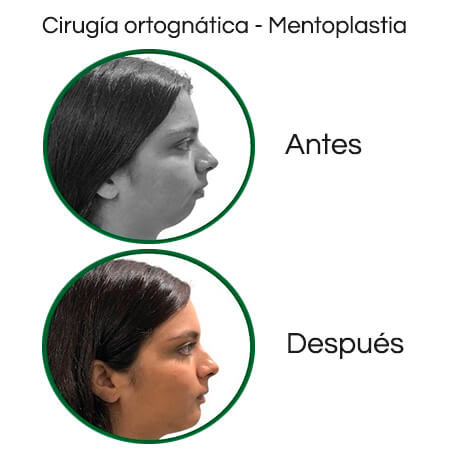

Galería de antes y después